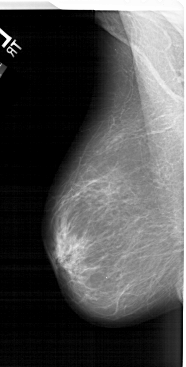

LEFT_MLO LINES 6601 PIXELS_PER_LINE 3331 BITS_PER_PIXEL 12 RESOLUTION 43.5 NON_OVERLAY